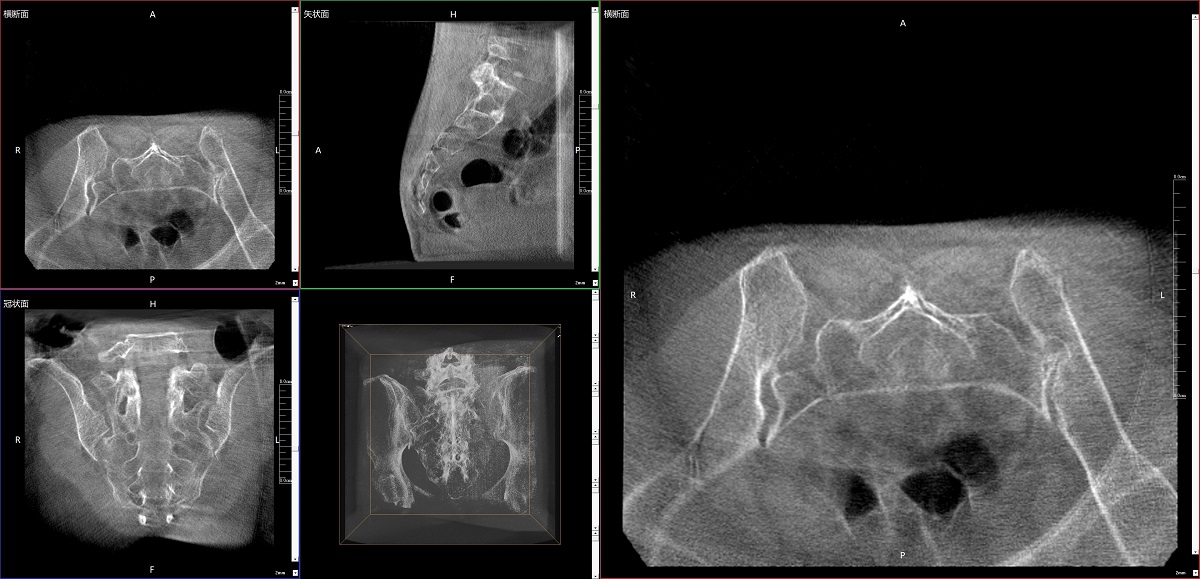

在骨科手術中,影像相當于醫(yī)生的“眼睛”,要先“看得清",才能“算得準” “打得穩(wěn)”。普愛醫(yī)療第三代平板三維C形臂協(xié)同醫(yī)院創(chuàng)傷導航機器人已開展多例“骨盆骨折微創(chuàng)手術”,成為上海市第七人民醫(yī)院手術技術創(chuàng)新的一大亮點。

普愛醫(yī)療第三代平板三維C形臂出色的二維透視和術中三維成像效果,為機器人提供了精確的術中影像依據(jù),協(xié)同提升手術整體的精準度和效率,為患者帶來了更安全、更高效的醫(yī)療服務體驗。